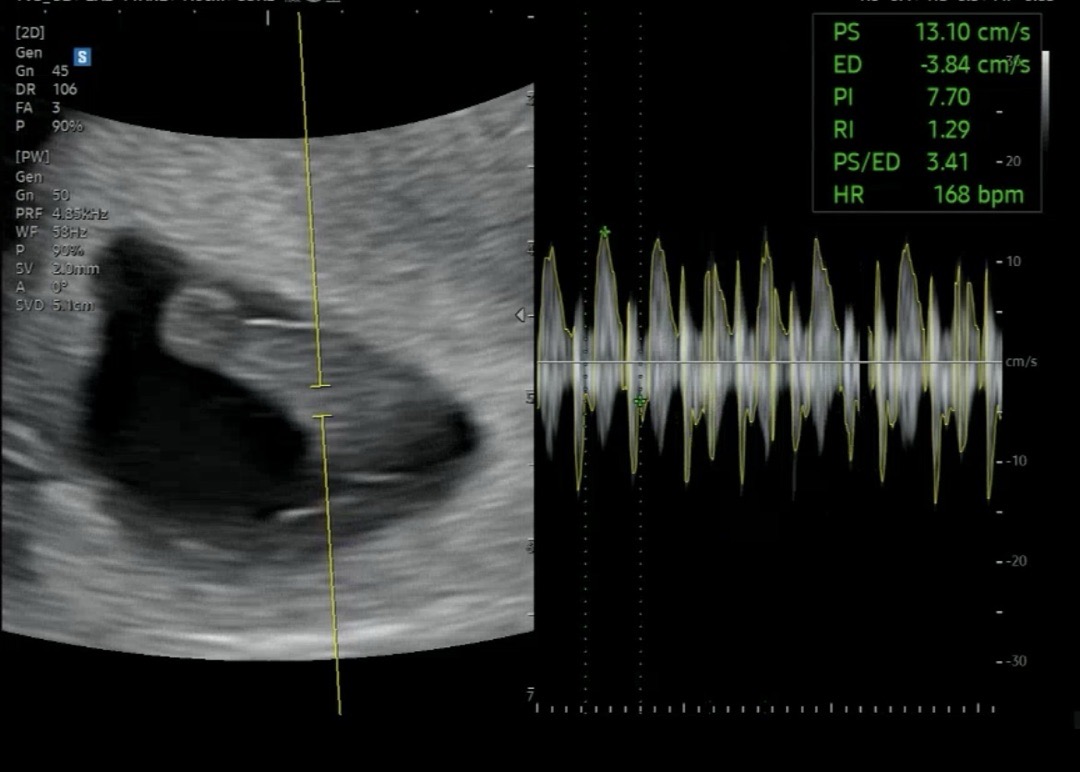

오늘 7주 4일차라서 심장소리 듣고왔어요! 명절에 차도 많이타고 조금 돌아다녀서 힘들었는데 ㅠㅠ 기특하게도 잘 크고있었어요 😍😍 다음진료일은 10주차인 , 약 3주뒤에 오래요 … ㅠㅠ 근데 저는 젤리곰 보고싶었는데 ㅠㅠ!!! 다들 젤리곰 보셨나요? 10주에 가면 젤리곰은 없겠죠? 병원비가 생각보다 만만치 않아서 젤리곰 굳이 보러 또 방문해야할지 고민이되네여 ,,,,,,,,